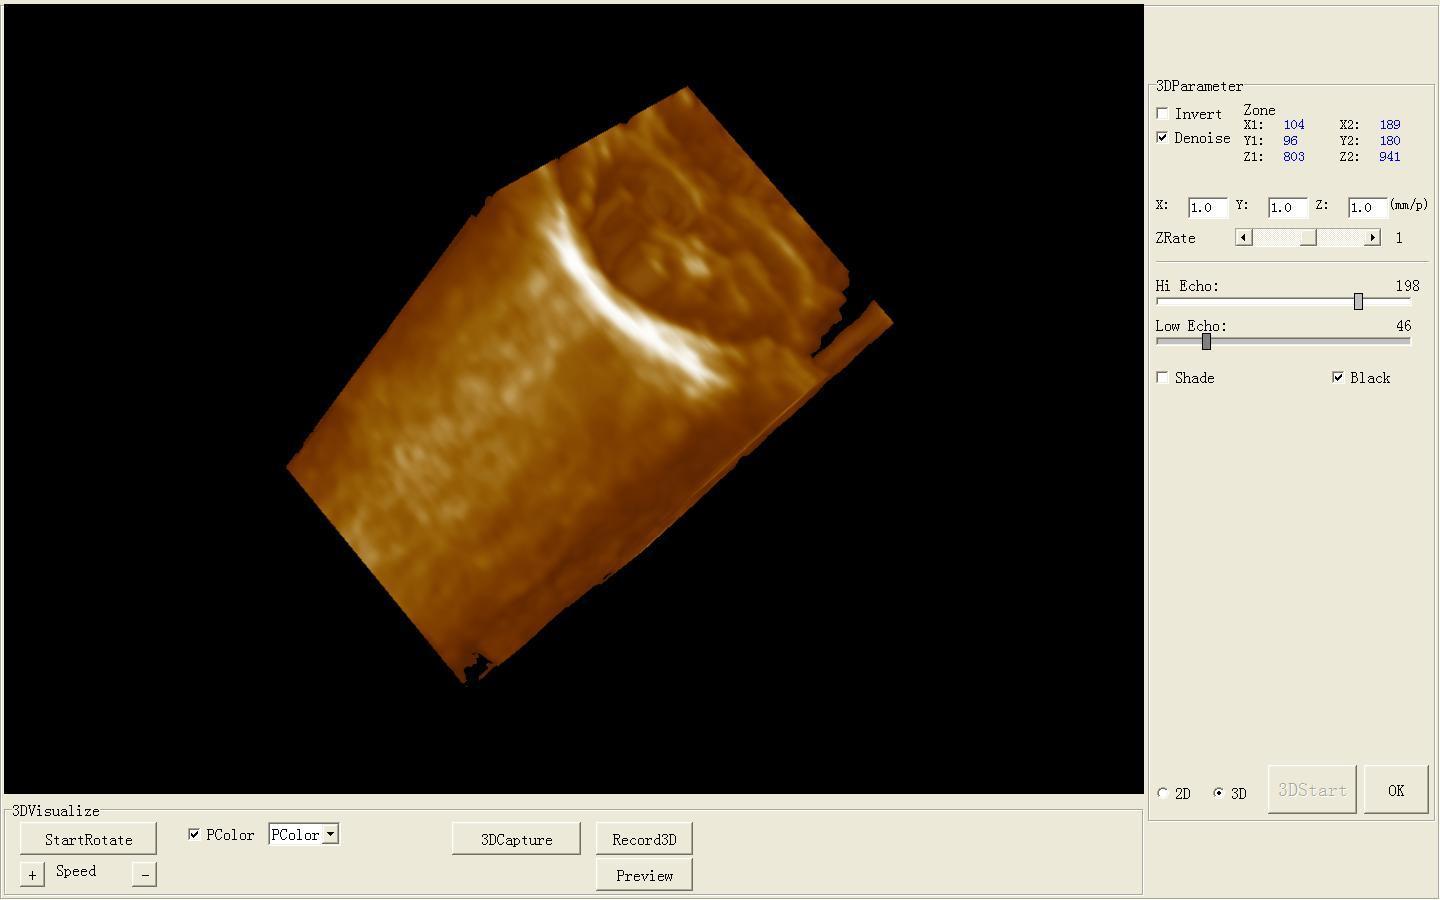

Full Digital Ultrasound Ultrasonic Scanner System 7.5 Mhz Linear Probe 3D image 190891058744

Model: RUS-9000B

software: NEW External 3D Software